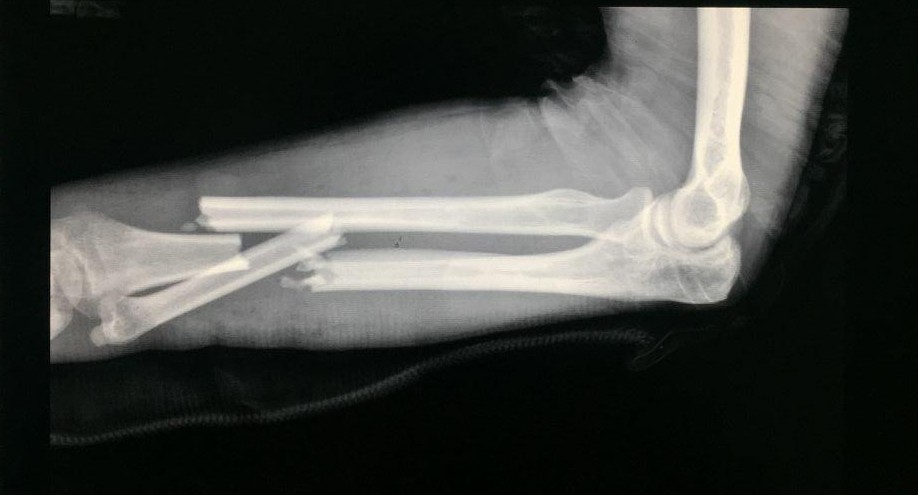

“送来我们这的时候,他的手臂肿胀、畸形,局部明显压痛,活动受限。”宜宾民心创伤骨科医院医师介绍,片子显示,“左尺桡骨中远端粉碎性骨折”,“相当于断成了四截,这需要超过一定限度的暴力。”

术前.jpg